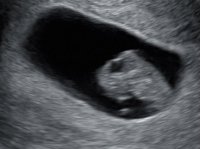

Åja, bare 6-7 ja...det var trist. Men fosteret og morkake flytter jo ikke på seg på de 14 dagene eller? Hmm, ble forvirret jeg nå. Men stemmer det at plasseringen hos meg tilsier gutt?Tror Uke 9 er for sent å bruke ramzi.. skal brukes i uke 6-7 helst

Hva tror dere? Innvendig uke 6+0

Dette bildet er fra innvendig mellom uke 7 og 8.